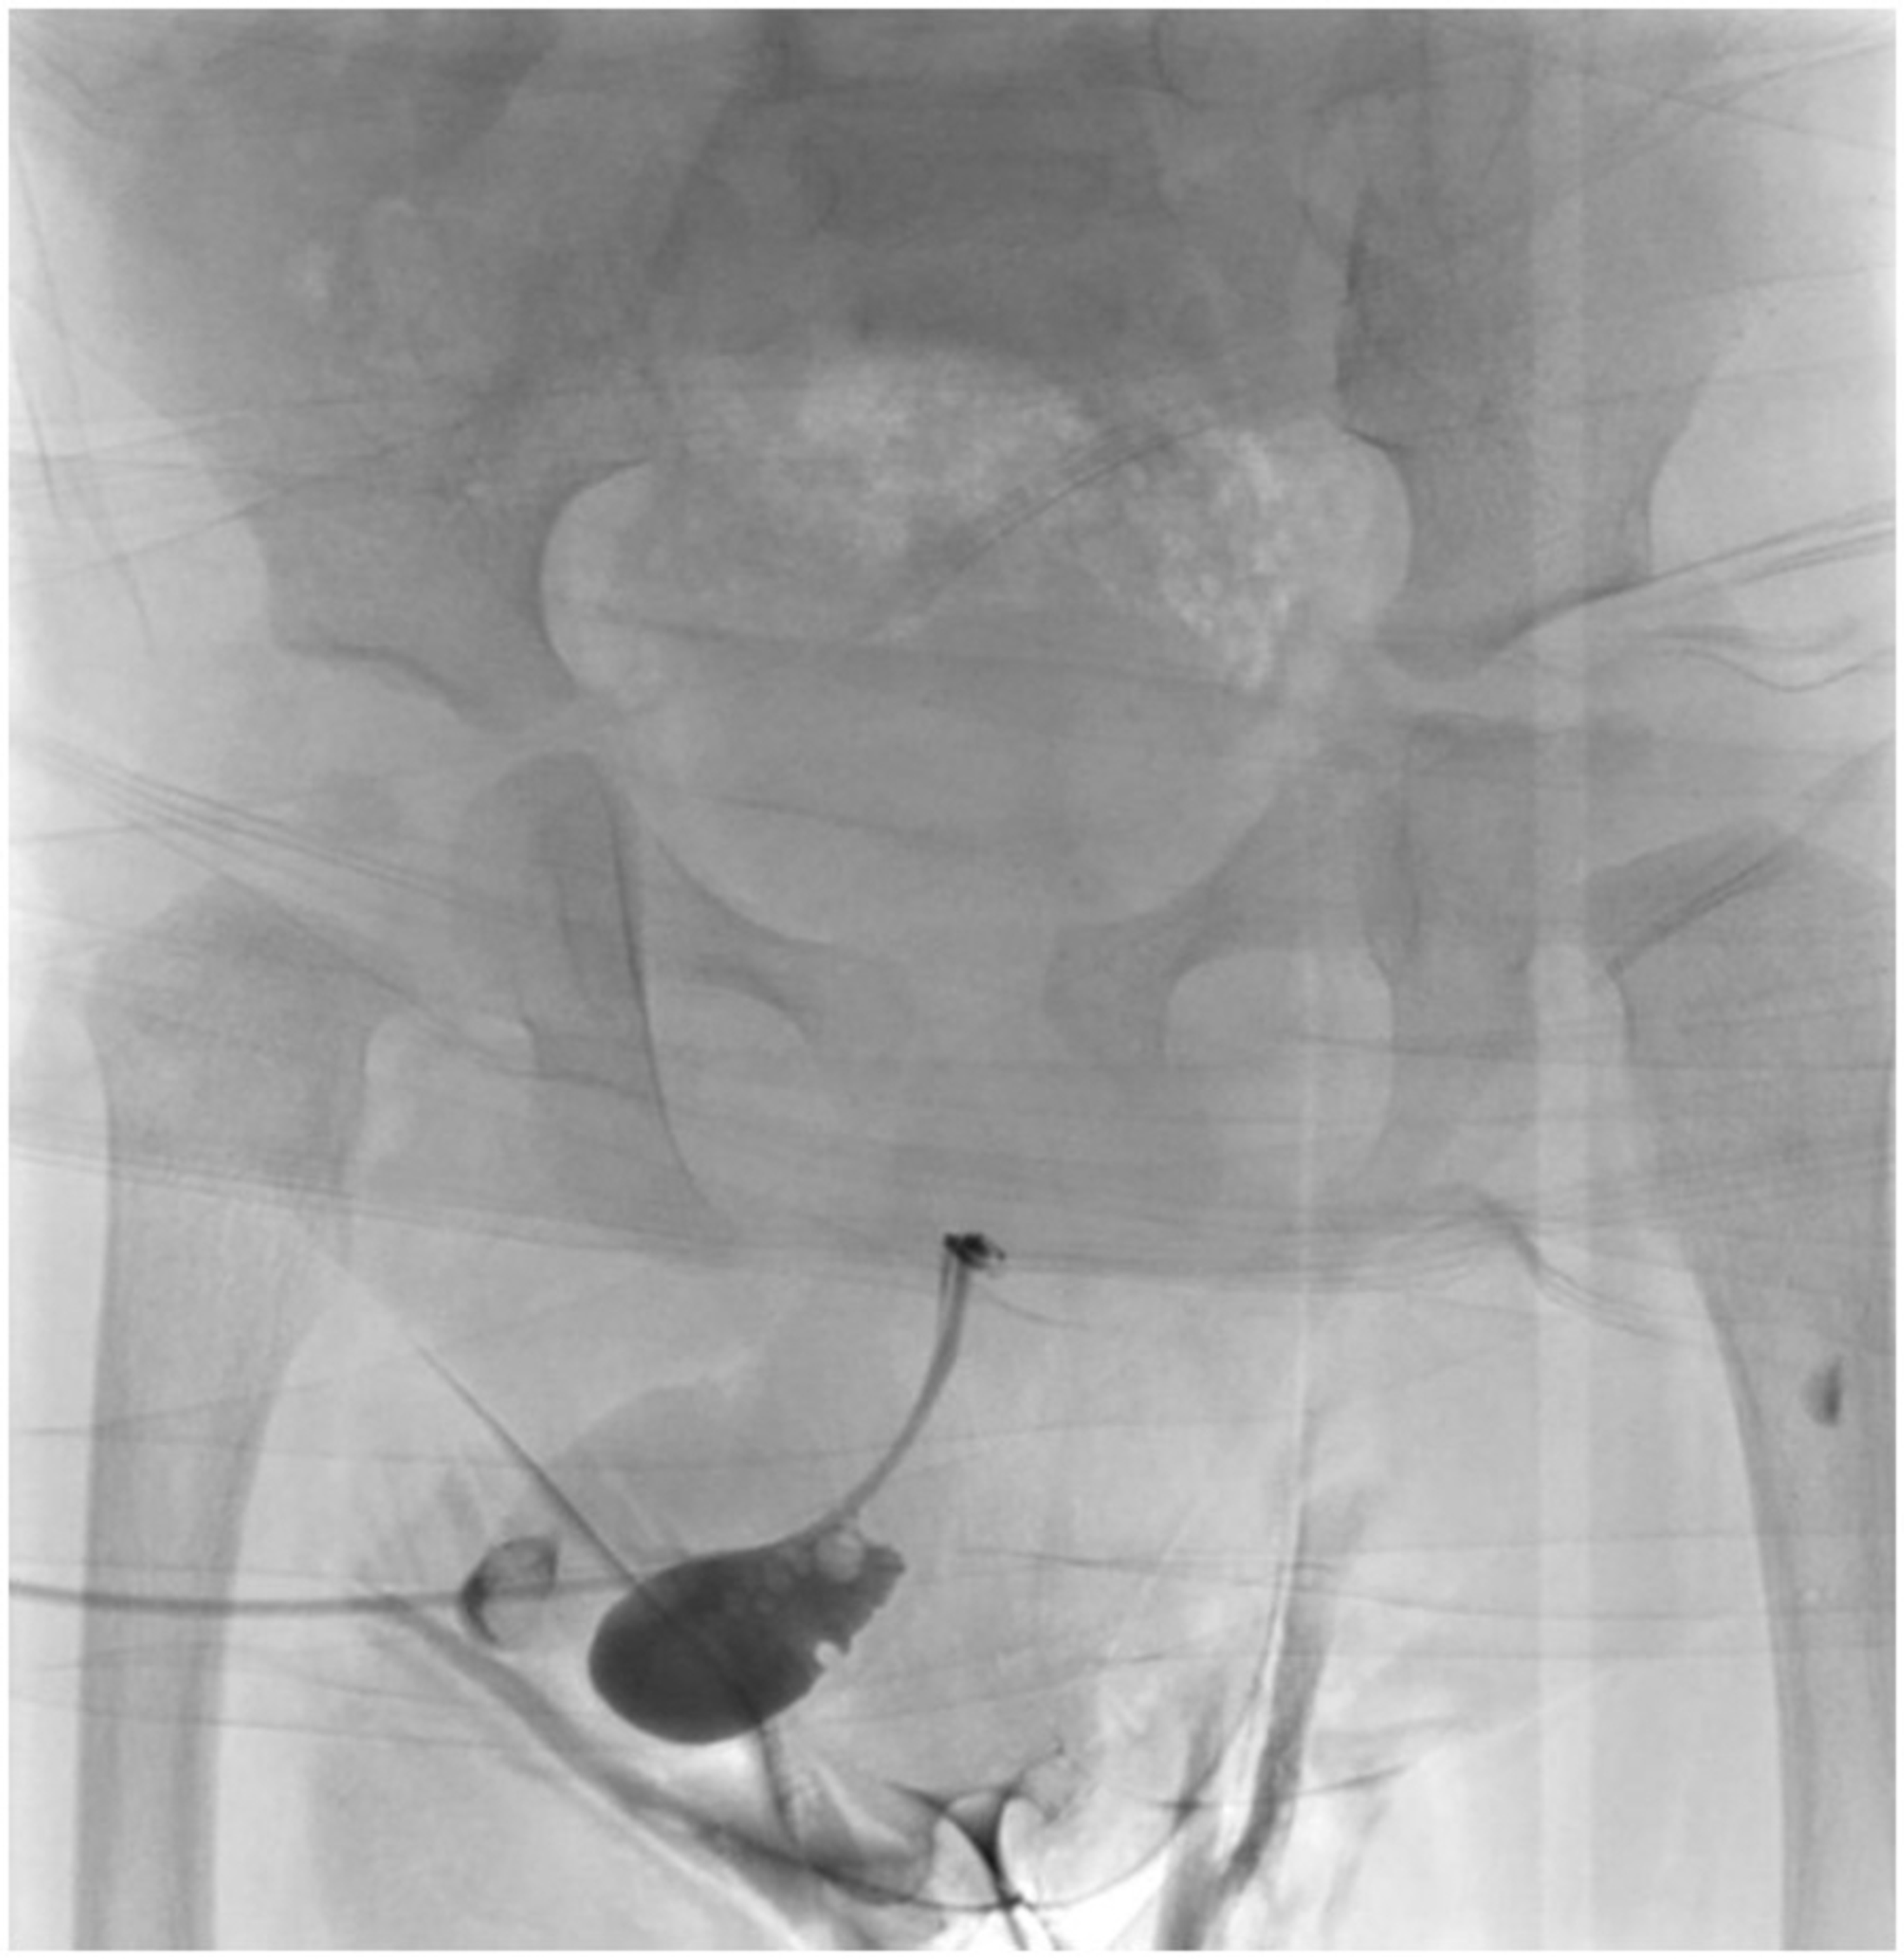

From www.researchgate.net

(PDF) Urethral diverticulum with proximal urethral stricture An What Is A Urethral Diverticulum Urethral diverticulum (ud) is a condition in which a variably sized “pocket” or outpouching forms next to the urethra. What is a urethral diverticulum? They should not be confused with a ureterocele of the distal ureter. Urethral diverticula, or urethroceles, are focal outpouchings of the urethra. The diagnosis and management of urethral diverticula (ud) present a challenge to the reconstructive. What Is A Urethral Diverticulum.